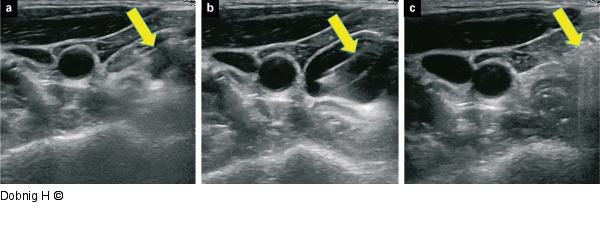

Abbildung 8a-c: Alkoholablation - Schilddrüse (a): Alkohol wird instilliert, es bilden sich kleine echoreiche, wolkige Gebilde, die nach Beendigung der Instillation (b) wieder aufklaren. (c) Zyste nach vollständiger Aspiration des Alkohols. Pfeile zeigen zur Nadel. |

(a): Alkohol wird instilliert, es bilden sich kleine echoreiche, wolkige Gebilde, die nach Beendigung der Instillation (b) wieder aufklaren. (c) Zyste nach vollständiger Aspiration des Alkohols. Pfeile zeigen zur Nadel. |